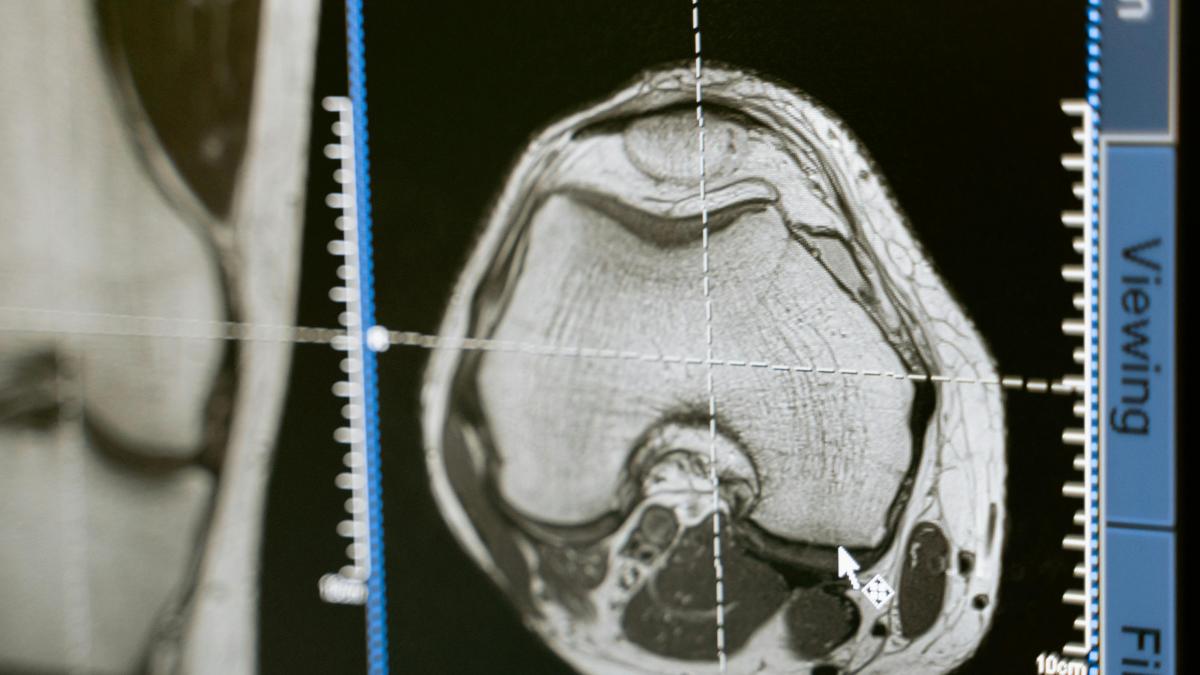

În cadrul cercetării se realizează, totodată, şi o encefalogramă cantitativă care arată cum funcționează creierul. "Vedem toate ariile creierului și să vedem care e factorul comun, până la urmă, al acestor tineri. Este vorba despre tinerii din campania 100 de tineri pentru dezvoltarea României, deja cunoscuți pentru performanțele lor în artă, leadership, tehnologie și inovație.